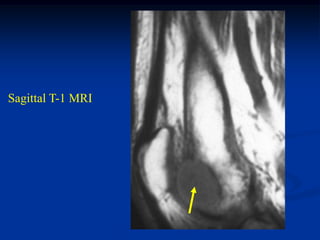

Case #1130            Metastatic Renal Cell

45 year male with metastatic renal cell CA to os calcis

Sagital T-1 MRI

tumor

Sagittal T-2 MRI

Axal T-1 MRI

Axial T-2 MRI

Photomic